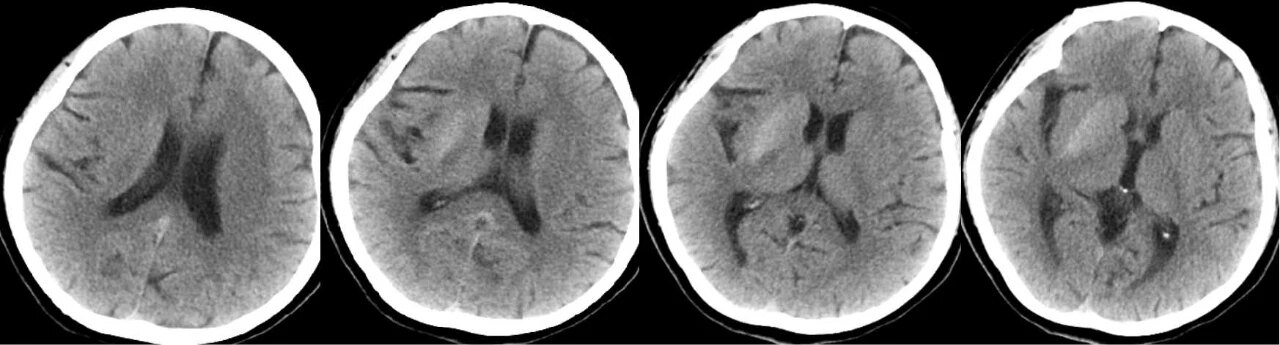

急诊头颅 CT 图像如下:

CT 示右侧尾状核头及豆状核弥漫性高密度,边界清晰,内囊密度无明显异常。

女,58 岁,非酮症高血糖性偏侧舞蹈病。CT 示右侧尾状核头及豆状核弥漫性高密度。MRI T1WI 示病灶呈高信号,T2WI 呈低信号,边界清晰。病理切片示右侧基底节出血。